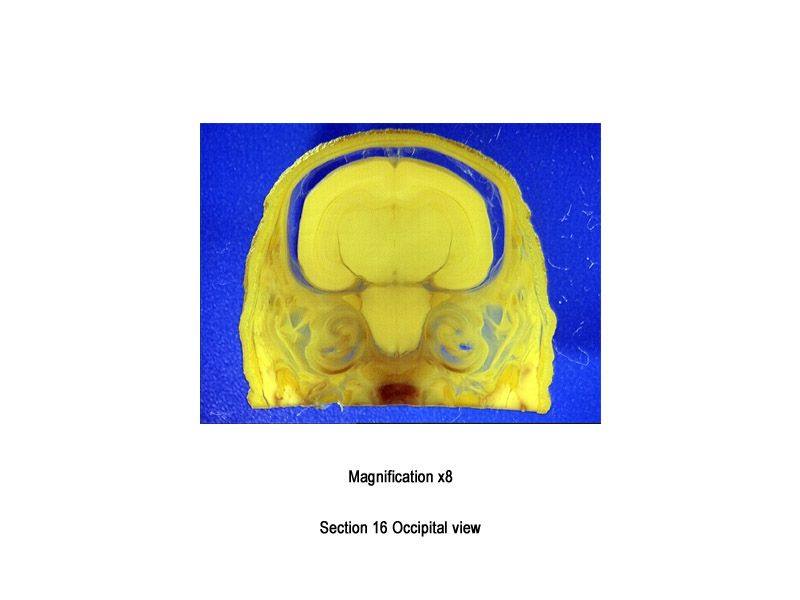

Anatomical description requires the use of a series of terms to denote angles, views, axes, planes and directions. As with the nomenclature of structures, there are various conventions. The terms cranial (or dorsal) and caudal (or ventral) are used to denote the upper and lower regions of the head, respectively. "Rostral" is used to denote the nasal extremity of the head and "occipital" to denote the back of the head (the region at the junction of the head and neck).

The images below show the normal appearance of Bouin's fluid fixed head sections in specimens at Day 29 of gestation (day mating observed = Day 0).

It is essential that both sides of each section is examined so that structures that exist is several sections can be visualised by the examiner in their mind as 3D.